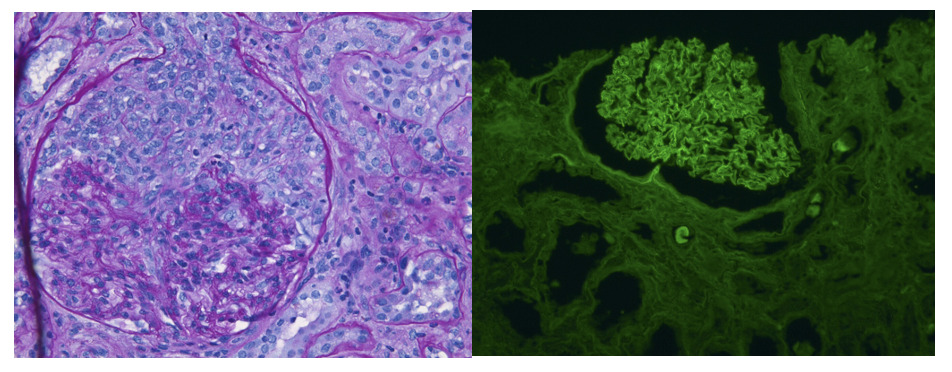

The nephrology team was consulted, leading to the detection of reactive ANA, positive p-ANCA, anti-MPO, and anti-GBM antibodies (MPO titer was elevated at 168 AU/ml and anti-GBM elevated at 59). Renal pathology showed crescentic injury in 63% of glomeruli with weak glomerular basement membrane staining, consistent with anti-GBM antibodies; the predominance of cellular to fibrocellular crescents suggested a pauci-immune process associated with ANCAs (Figure 1). Given these findings, the care team concluded a likely diagnosis of RPGN with positive serological markers. The patient received a steroid pulse with solumedrol 1 g daily for 3 days, then transitioned to prednisone 60 mg daily. Cyclophosphamide 75 mg PO daily and plasmapheresis (PLEX) were also initiated as separate therapies. Her first PLEX session was conducted shortly after renal biopsy, following successful placement of a permanent catheter. Hemodialysis (HD) was initiated the following day due to worsening hyponatremia, declining renal function, and changes in mental status. The patient followed a schedule of alternating PLEX and HD treatments throughout her inpatient stay.

Anti-GBM disease is a rare autoimmune disorder caused by autoantibodies targeting the non-collagenous (NC1) domain of type IV collagen, a key structural component of the glomerular and alveolar basement membranes.2 Diagnosis relies on detecting circulating anti-GBM antibodies, typically via ELISA, and confirming with renal biopsy, which classically shows linear IgG deposition along the glomerular basement membrane. In patients with or without ANCA, anti-GBM antibodies target the same regions of type IV collagen (particularly the alpha-3 chain), suggesting a shared immunologic trigger regardless of ANCA status.3 Anti-GBM disease occurs in <1 case per million per year, with peak incidence in the third and sixth-seventh decades. Younger patients more often present with pulmonary-renal syndrome and have a slight male predominance, while older patients typically have isolated renal involvement and are more likely to be dual-positive for ANCA and anti-GBM.1,4,5 The exact cause remains unclear, but environmental exposures such as smoking, infections, hydrocarbon exposure, and certain medications have been implicated.6 No specific trigger was identified in this patient. In this case, the presence of anti-GBM antibodies, along with positive p-ANCA and anti-MPO antibodies, strongly supported the diagnosis. The renal biopsy confirmed crescentic glomerulonephritis with significant interstitial fibrosis and tubular atrophy, findings consistent with advanced disease.

The authors of this manuscript would like to thank Dr. Anthony Chang, Director of University of Chicago MedLabs, for providing the images of the patient’s kidney biopsy.